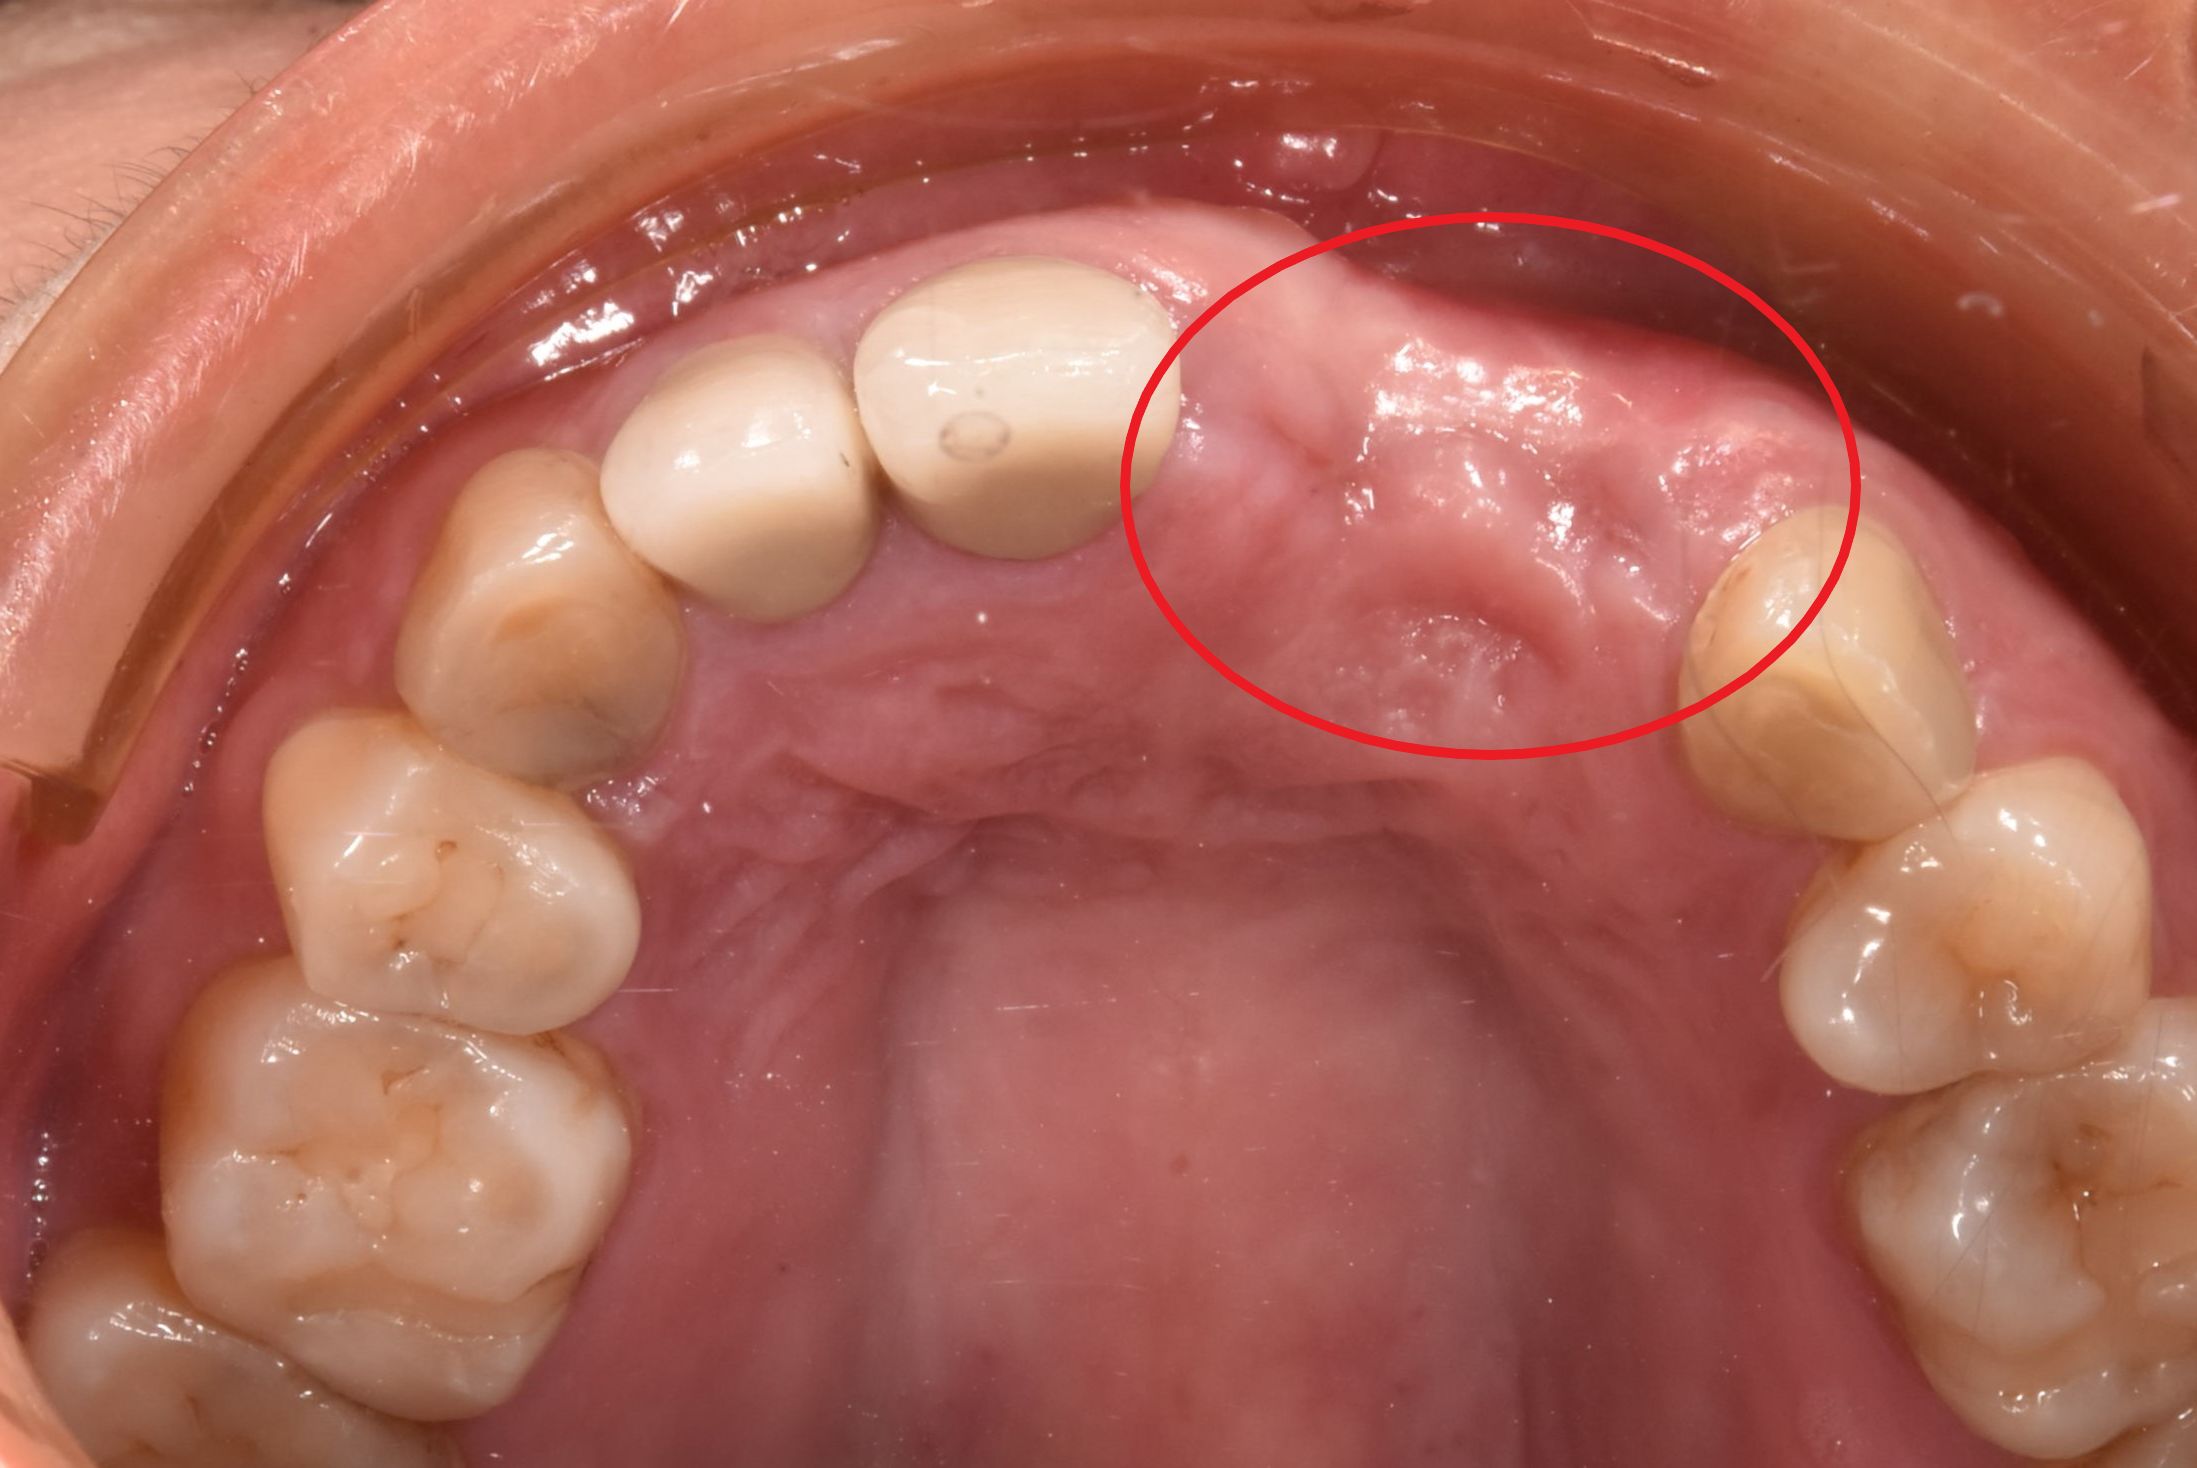

案例二

骨頭明顯凹陷